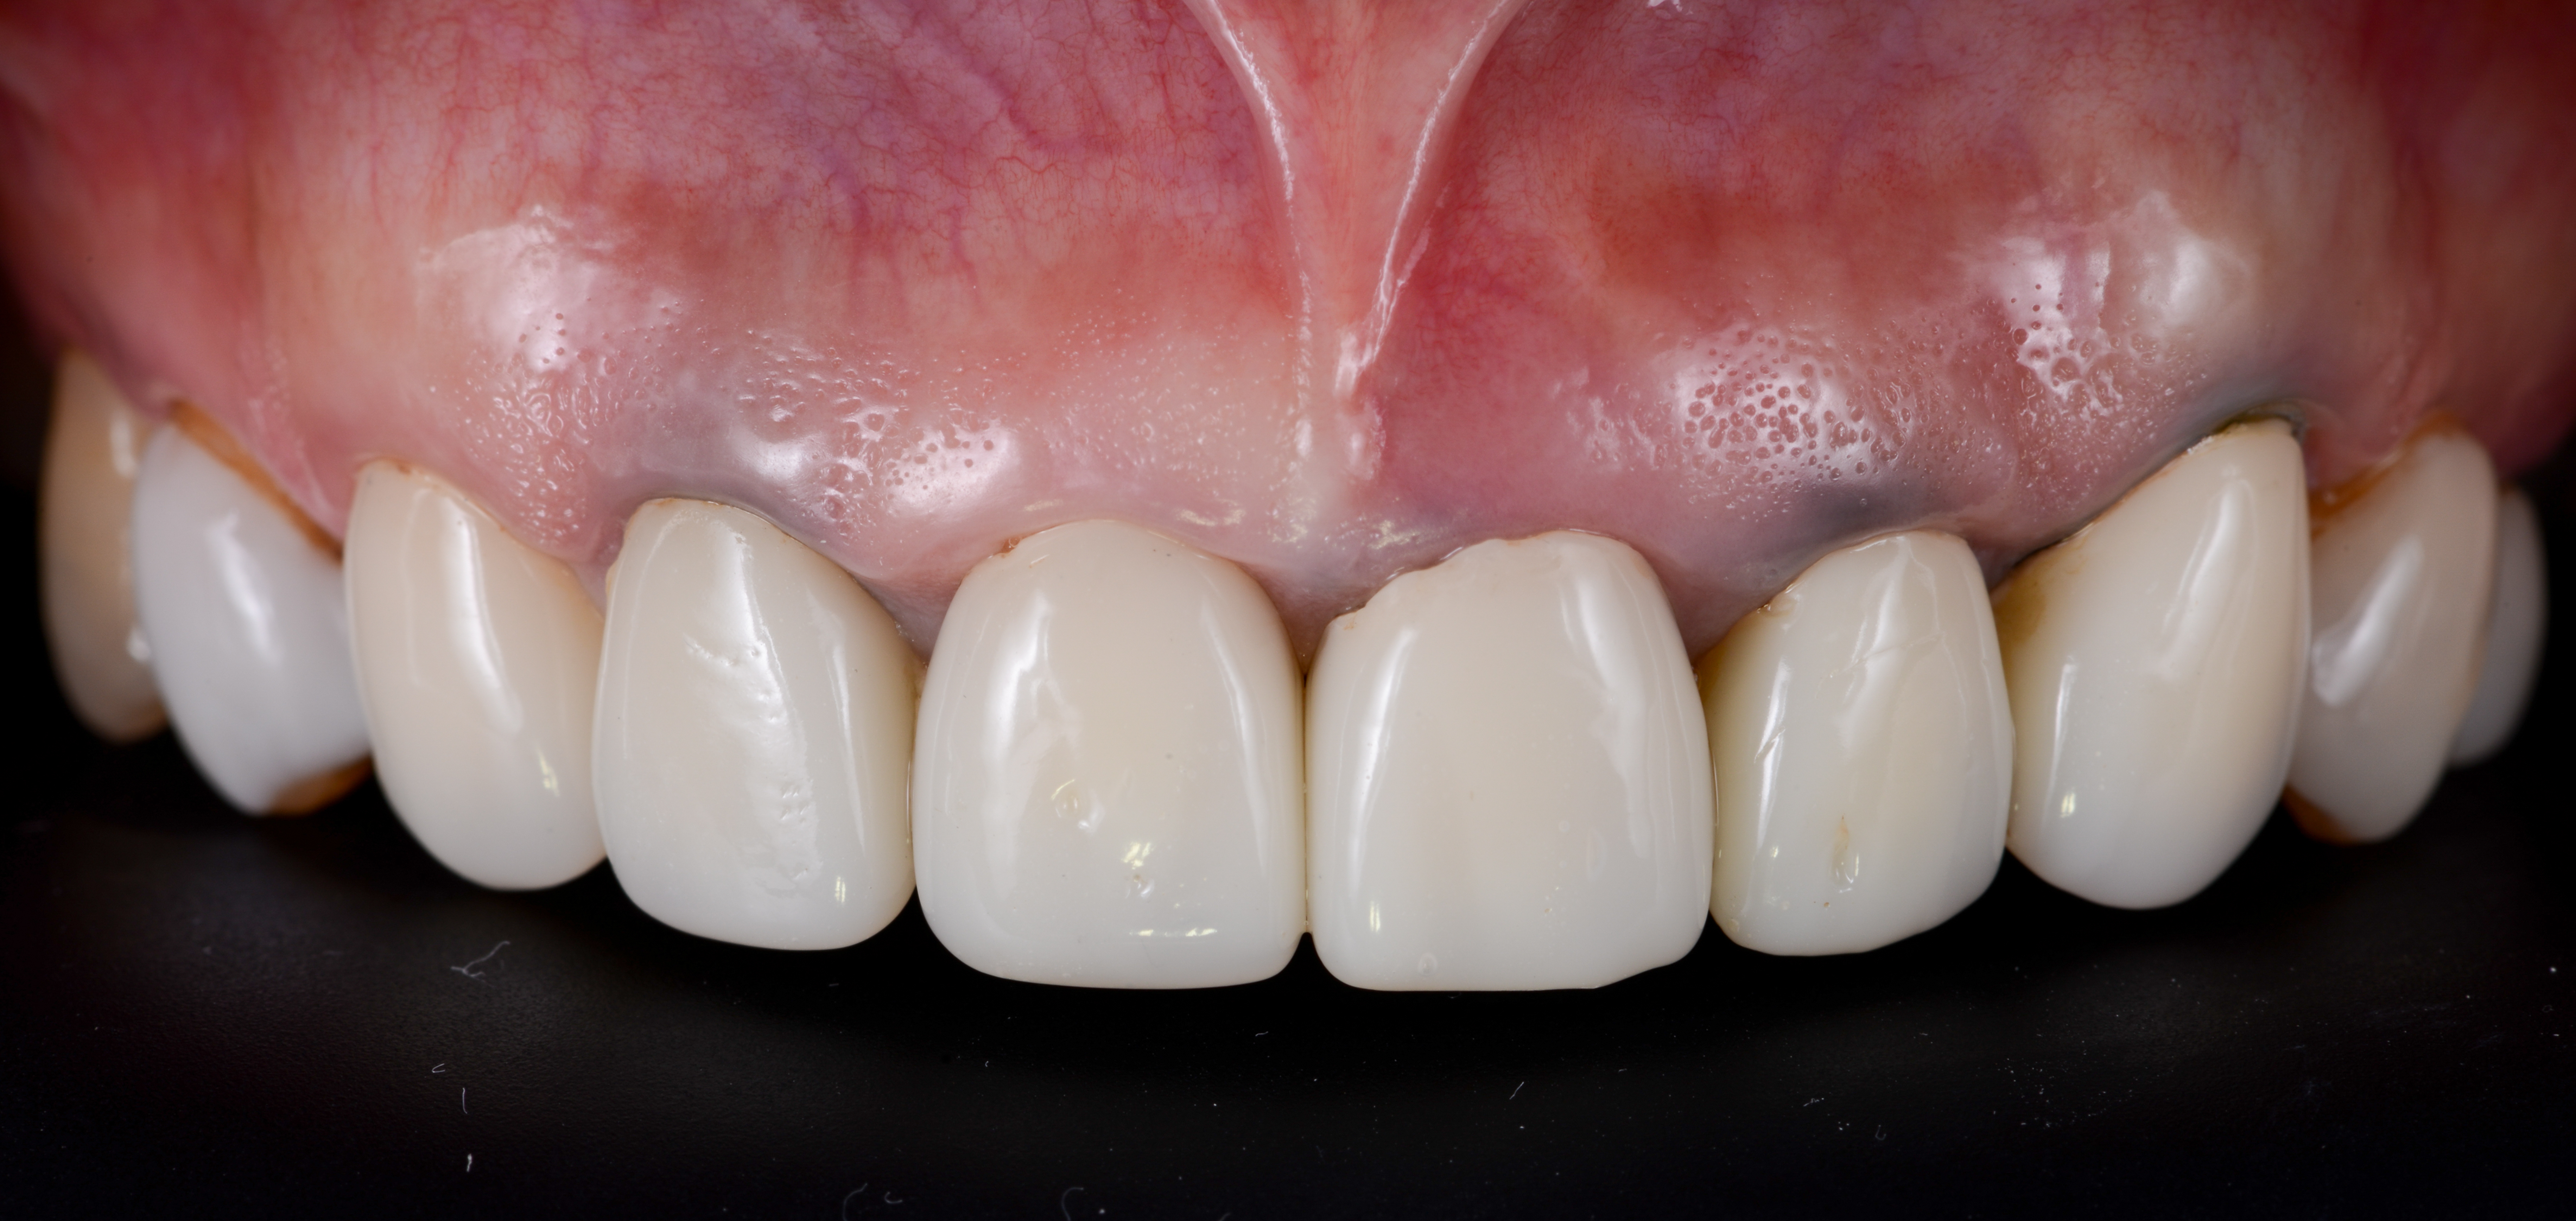

ガミースマイルを歯周形成外科で改善した症例

- 年代、性別 27歳・女性

- 来院動機 ガミースマイルを治したい

- 治療内容 歯周形成外科